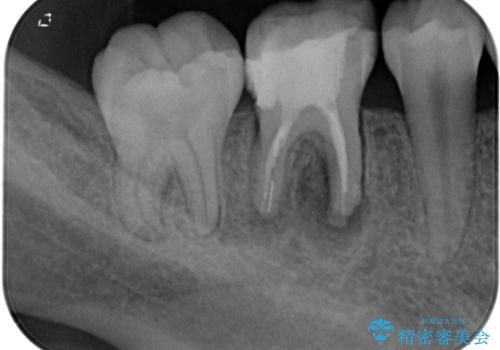

下顎大臼歯は根管治療がされている歯が咬合時に痛みを感じ、上顎の大臼歯2歯は冷たいものがしみる状態でした。

根管治療を行った歯の周辺にある病変は数ヶ月後にレントゲン写真を撮って確認する必要があるため、今後経過観察を行っていく予定です。